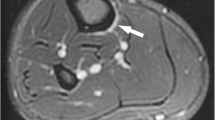

She had no previous bone stress injuries and no specific metabolic bone risk factors were identified. On examination, there was palpable bony irregularity in the middle third of the right tibia anteriorly with mild tenderness over this area. A right tibial radiograph revealed focal cortical thickening in the mid-tibial diaphysis anteriorly with a lucent line extending through the anterior cortex in keeping with a stress fracture (Fig. 1a).

(a) Lateral radiograph of the right tibia showing focal cortical thickening with a horizontal lucency in the anterior cortex of the mid tibia indicating an incomplete stress fracture (arrowhead). MRI Sagittal STIR (b) and T1 weighted images (c) showing focal cortical thickening but no periostitis, fracture line or evidence of marrow oedema (arrows). (d) Sagittal CT reformat of right tibia demonstrating presence of horizontal fracture line (arrow) seen on the radiograph

A subsequent MRI showed no evidence of bone oedema or periosteal reaction (Fig. 1b, c). Computer tomography (CT) confirmed the presence of the fracture (Fig. 1d). Dual energy x-ray absorptiometry (DEXA) showed a T-score within the normal range. Following 6 months of conservative management with complete resolution of tenderness and confirmation of bony union on CT. She successfully gradually returned to running.